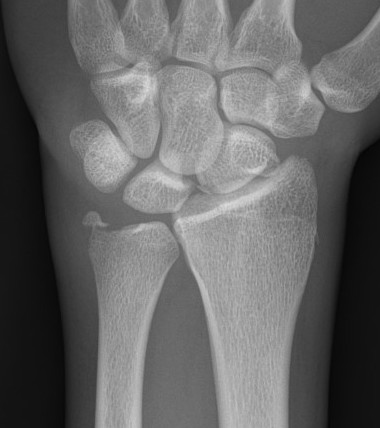

Distal radius fracture with DRUJ instability

Management

DRUJ instability after distal radius fracture ORIF

- 100 cases of DRUJ instability after distal radius ORIF

- 50 treated with arthroscopic capsular repair

- 50 treated in cast

- better outcomes with capsular repair

www.boneschool.com/distal-radius-fractures